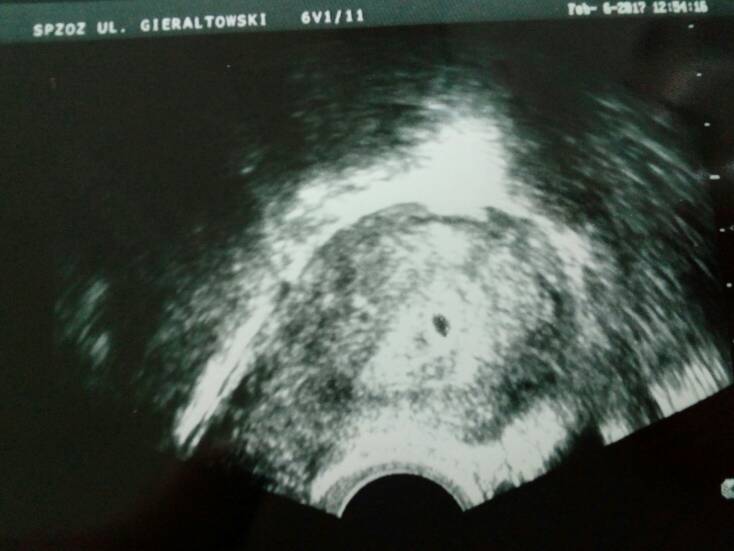

Pęcherzyk rośnie 5tc 1 dzień dziś go szło zmierzyć , dokładnie ma 5.28mm , dostalam badania na nfz za 3 tygodnie mam tu na wizytę przyjść

1486379207-aaaaaa.jpeg